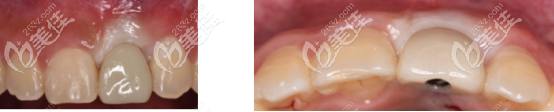

然后安裝臨時基臺+樹脂冠,用螺絲固位?;颊邔ρ拦诘念伾庑?,舒適度都比較滿意

總結:active種植體,不需要頻繁的更換鉆頭,所以在操作上就比較簡單,而且對牙齦的壓迫感小,穩(wěn)定性也優(yōu)于其他種植體。